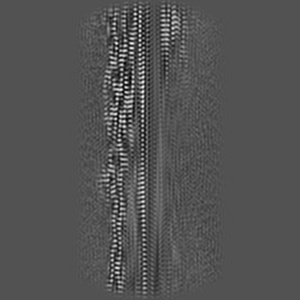

Complex fibril structure of MSA alpha-synuclein with CNS-11g at 15 hours

The small molecule CNS-11g forms amyloid-like fibrils that disassemble pathological alpha-synuclein fibrils